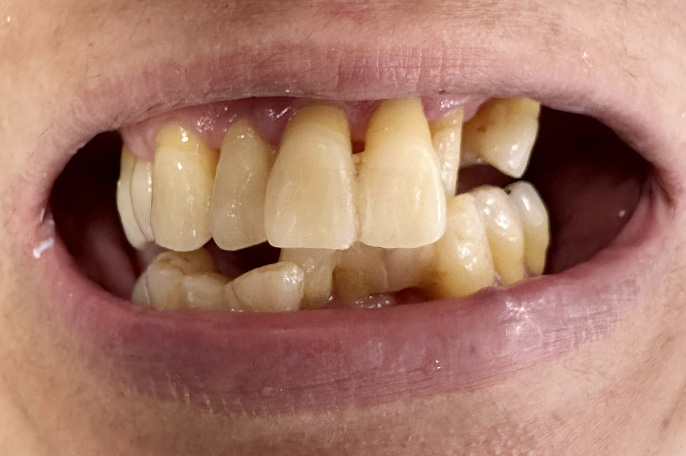

オールオン4 症例・48歳女性主訴:上下の歯を綺麗にしたい。

口の中がボロボロでマスクが外せないという患者様です。上下オールオン4にて治療しました。上下4本ずつインプラントが入っています。即日で綺麗な仮歯が入って満足していただけました。

術前

術後